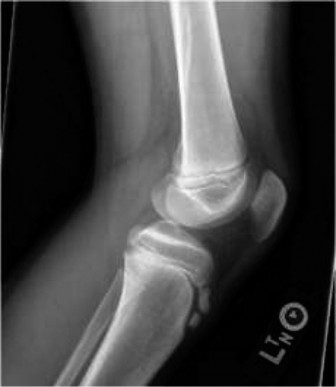

Standard orthogonal radiographs of the ankle, including anteroposterior, lateral, and mortise views, are the initial diagnostic modality. However, the complex, multi-planar nature of transitional fractures makes plain radiography insufficient for definitive preoperative planning. Plain films frequently underestimate the degree of articular displacement and the number of fracture fragments.

A high-resolution Computed Tomography scan with sagittal, coronal, and three-dimensional reconstructions is mandatory for all suspected triplane and Tillaux fractures. The CT scan allows the orthopedic surgeon to precisely map the fracture lines, quantify the articular step-off, identify the presence of intercalary articular fragments, and plan the exact trajectory for internal fixation. In a triplane fracture, the CT scan will clearly delineate the coronal metaphyseal fragment, the sagittal epiphyseal fragment, and the axial physeal separation. Identifying the exact location of the Chaput fragment and the integrity of the syndesmosis is critical for determining the surgical approach and the necessity of syndesmotic stabilization.